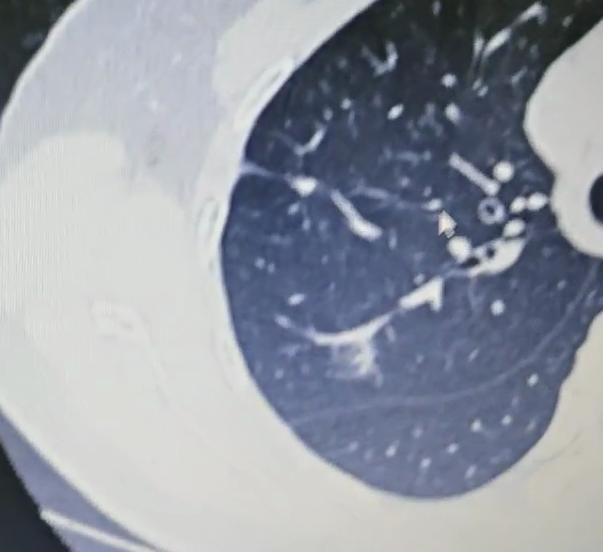

肺结节随访别漏这个细节,小心进展被忽略!不少人查出肺小结节,特别是磨玻璃结节后,医生都会建议定期动态观察。 大家心里普遍有个想法,只要结节不增大就没什么风险,等真出现变化了再做手术也来得及。 但这里藏着一个特别容易被忽略的细节,很多人就是因为没注意到它,等到察觉结节有进展时,已经错过了最佳的观察和干预时机。 其实判断肺结节有没有变化,不单单看单次复查的结果,核心关键在于对比的方式是否到位。医生通常会结合结节的大小和密度,制定不一样的随访周期。 要是磨玻璃结节偏大,密度也相对高一些,部分医生会建议缩短随访间隔,大概每3个月复查一次; 如果结节密度很淡,尺寸也只有几毫米,大多会推荐半年复查一次,这样既能及时监测结节动态,又能避免过度检查带来的负担。 每次复查结束后,一定要带着新旧CT片找医生做专业对比,重点排查结节的大小和密度是否有异常变化。 这里要特别提醒那些随访时间久的朋友,有些人为了监测结节,甚至坚持复查了十几年,这种情况下千万别只拿最近两次的片子对比。 就有这样一位患者,半年内的两次片子对比下来没发现明显异常,可医生调出他三年前的片子,和最新的片子在电脑上逐一比对后,发现结节密度已经明显升高,这种情况就必须及时通过手术处理。 之所以反复强调这个对比细节,是因为像原位癌、微浸润癌这类结节,生长速度通常都很慢。如果只对比近期的两次片子,大概率看不出明显波动,但长期累积下来,结节其实已经在悄悄进展了。 很多患者就是因为忽视了这种长期对比的重要性,最终错过早期干预的最佳窗口。 正在随访肺结节的朋友们,复查时一定要记牢,务必把最新的片子和最早的片子一起带给医生。只有通过全面的纵向对比,才能准确判断结节的真实情况。这个看似不起眼的小细节,直接决定了对结节进展的判断是否准确,千万不能掉以轻心。[玫瑰][作揖]